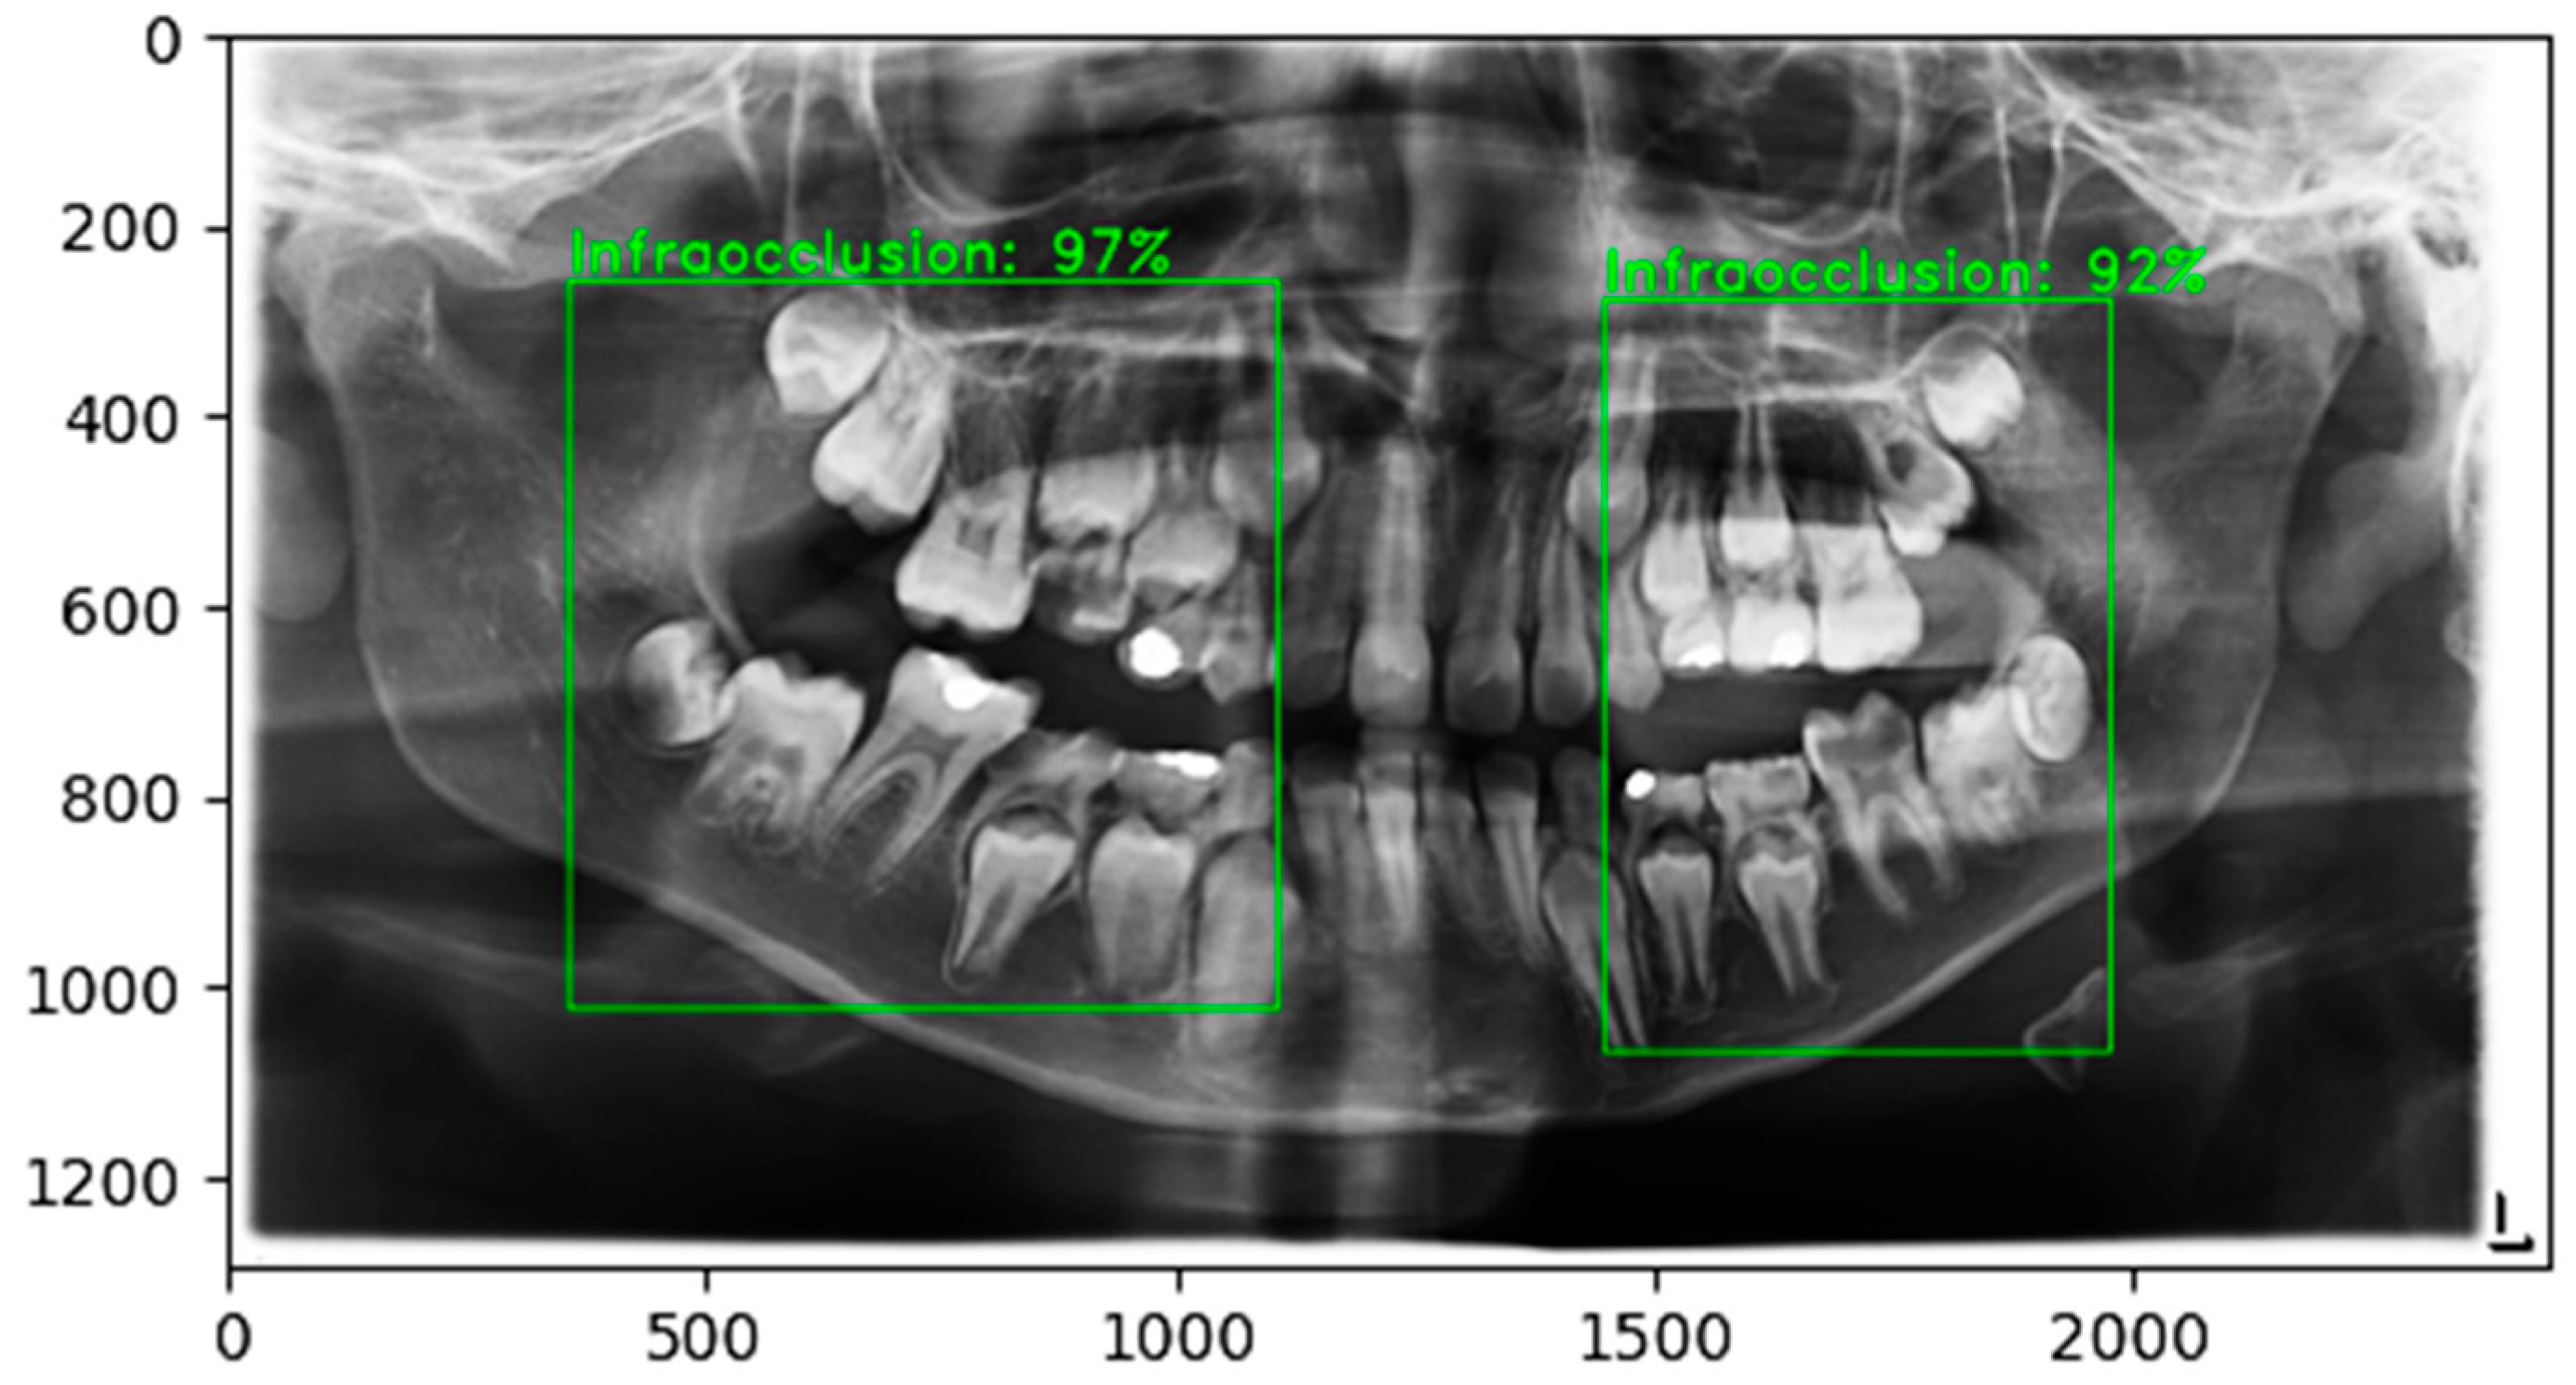

1.2. Related Works

4.3. Classification Performance and Overall System Accuracy